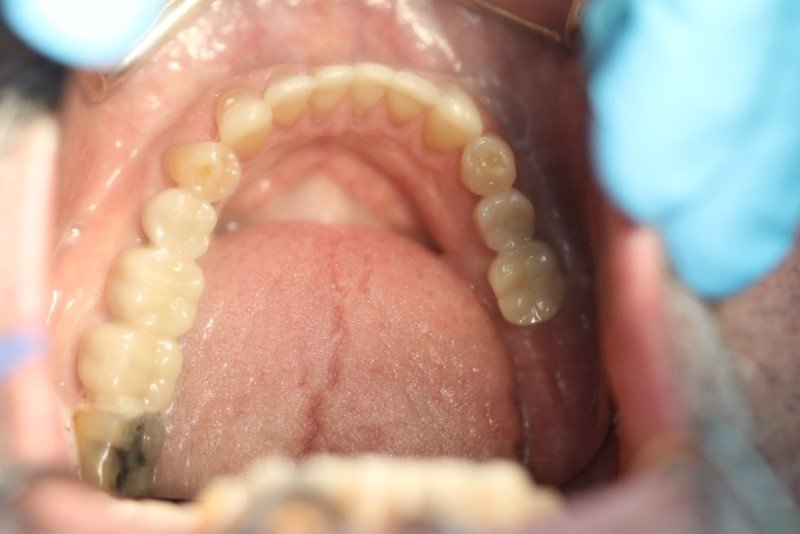

Treatment to restore all the implants has begun, and the patient has had his lower teeth replaced.